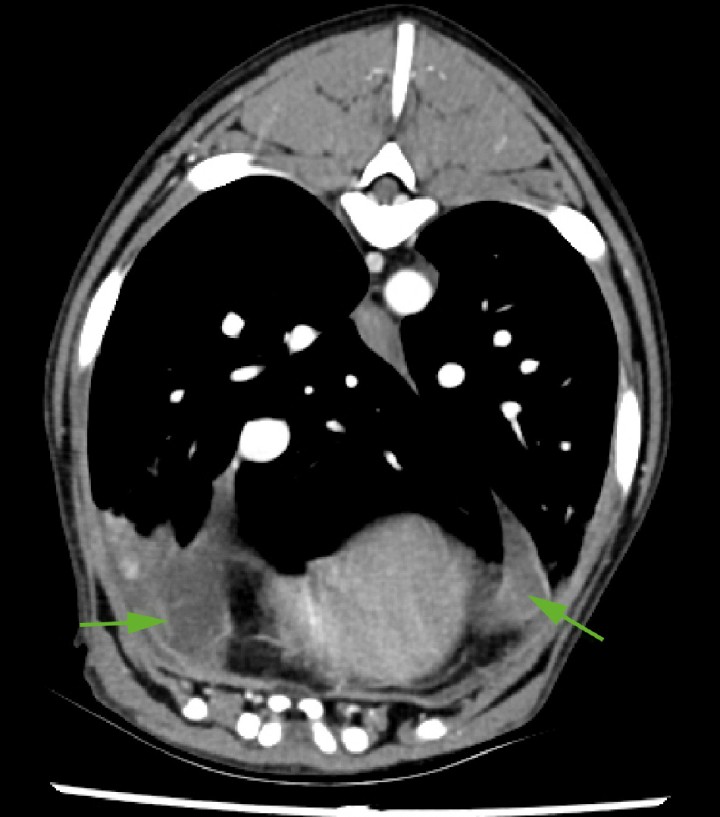

<p>Imagen de TC en ventana tejido blando postcontraste de corte trasversal; a la entrada del tórax, se evidencian los linfonodos mediastínicos craneales y esternal (flechas) aumentados de tamaño, con márgenes bien definidos, parénquima homogéneo, atenuación (50 UH) en fase precontraste y captación de contraste homogénea y moderada. Se aprecia, además, ligera hiperintensidad de la grasa perinodal.</p>

Imagen de TC en ventana tejido blando postcontraste de corte trasversal; a la entrada del tórax, se evidencian los linfonodos mediastínicos craneales y esternal (flechas) aumentados de tamaño, con márgenes bien definidos, parénquima homogéneo, atenuación (50 UH) en fase precontraste y captación de contraste homogénea y moderada. Se aprecia, además, ligera hiperintensidad de la grasa perinodal.